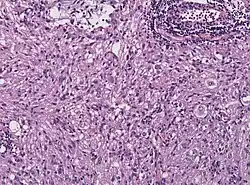

Histologisch ist dieser Tumor durch die außergewöhnliche Pleomorphie, d. h. eine Vielgestaltigkeit der glialen Tumorzellen charakterisiert. Mitosefiguren kommen vor, Nekrosen werden jedoch (im Gegensatz zum Glioblastom) gewöhnlich nicht beobachtet. Die Tumorzellen können Lipideinlagerungen enthalten (xanthomatöse Umwandlung) und sind von Retikulinfasern umgeben. Die immunhistochemische Färbung für GFAP belegt den glialen Charakter des Tumors.[6] Obwohl aufgrund des charakteristischen histologischen Bildes die diagnostische Abgrenzung gegenüber anderen Hirntumoren gewöhnlich keine Schwierigkeiten bereitet, kann die ausgeprägte Pleomorphie des Tumors insbesondere in der intraoperativen Schnellschnittuntersuchung zur Fehldiagnose eines Glioblastoms verleiten.